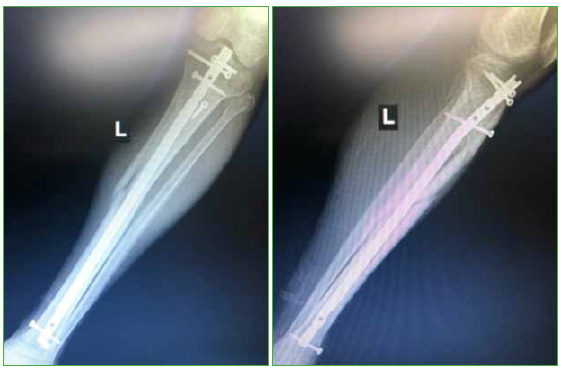

Se logro la consolidacion osea en todos los casos, en un tiempo promedio de 5 meses (minimo 3, maximo 10). Un paciente (4%) con una fractura segmentaria (caso 4) requirio un aumento del foco proximal con una placa sobre el clavo mas el aporte de injerto oseo autologo para lograr la consolidacion osea (Figura 5).

Figura 5.

Imagenes del posoperatorio alejado. Se observan signos de consolidacion con un correcto eje.